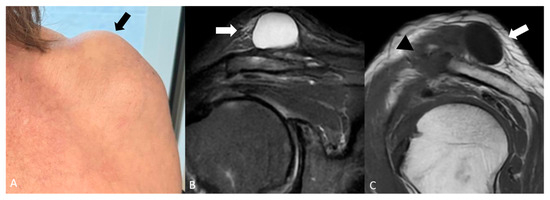

A typical cystic shoulder bump is the “geyser sign” (GS) (Figure 1), a characteristic imaging finding associated with chronic rotator cuff tears and degenerative changes in the acromioclavicular (AC) joint capsule. This sign is visualized as a fluid-filled collection above the AC joint, extending from the subacromial bursa through the compromised AC joint capsule into a subcutaneous space above the clavicle [16].

Figure 1.

(A) Elderly woman with a soft bump on the cranial portion of her right shoulder (black arrow). (B) coronal STIR and (C) sagittal T1-weighted showing a cystic lesion superior to the acromion-clavicular joint (white arrows). The lesion is raising subcutaneous soft tissue. Acromioclavicular osteoarthritis is noted (black arrowhead).